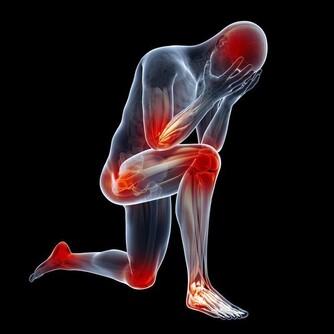

- 膝蓋、頸椎等關節部位特別容易受冷風侵襲,引起頸椎病、肩周炎、風濕、類風濕等。

4、休息時,關節暴露部位可適當加蓋毛巾被。每隔1小時活動身體,如搓手、按脖子、轉動關節等。